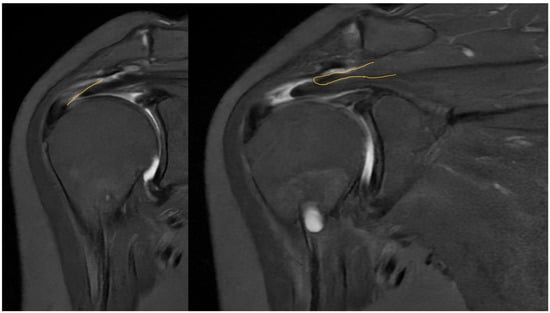

Taking a closer look at preoperative MR images, it is possible to glimpse the line of the tear, which is oblique, and the two sheets of the tendon, which have different degrees of retraction (Figure 12).

Figure 12.

Preoperative MRI with identification of the line of the tear and the two separated sheets of the supraspinatus tendon, with different retraction.

Preoperative magnetic resonance imaging can reveal the orientation of the tear, and the varying degrees of retraction in the tendon sheets. However, while imaging provides insight into tendon retraction, it does not yield information about the elasticity of the tissue, which can only be accurately assessed during an arthroscopic examination. Arthroscopy in the presented case revealed the separation of sheets 2 and 3 within both the infraspinatus and supraspinatus tendons. Both sheets of the infraspinatus tendon were deemed repairable, while sheet 2 of the supraspinatus tendon could not be adequately repositioned. Consequently, following the rotator cuff repair, a defect remained in the supraspinatus tendon, which the senior Author opted to address with the application of a Regeneten implant.